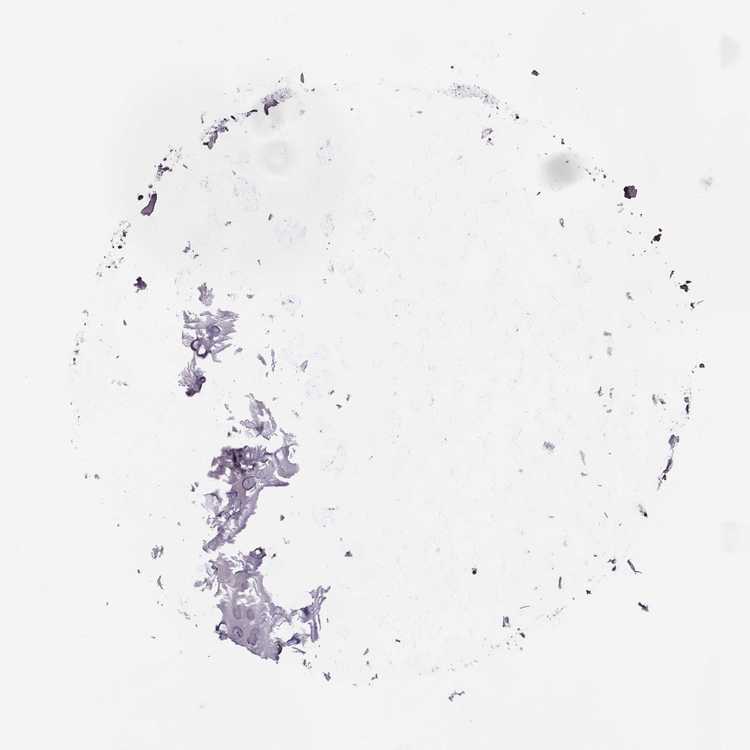

SOFT TISSUE 1 - Antibody stainingi

Antibody staining in the annotated cell types in the current human tissue is reported as not detected, low, medium, or high, based on conventional immunohistochemistry profiling in selected tissues. This score is based on the combination of the staining intensity and fraction of stained cells.

Each image is clickable and will lead to virtual microscopy that enables deeper exploration of all samples and also displays staining intensity scores, fraction scores and subcellular localization as well as patient and tissue information for each sample.

Antibody HPA056489

Chondrocytes Medium

Fibroblasts Low

SOFT TISSUE 2 - Antibody stainingi

Fibroblasts Medium

Peripheral nerve Not detected